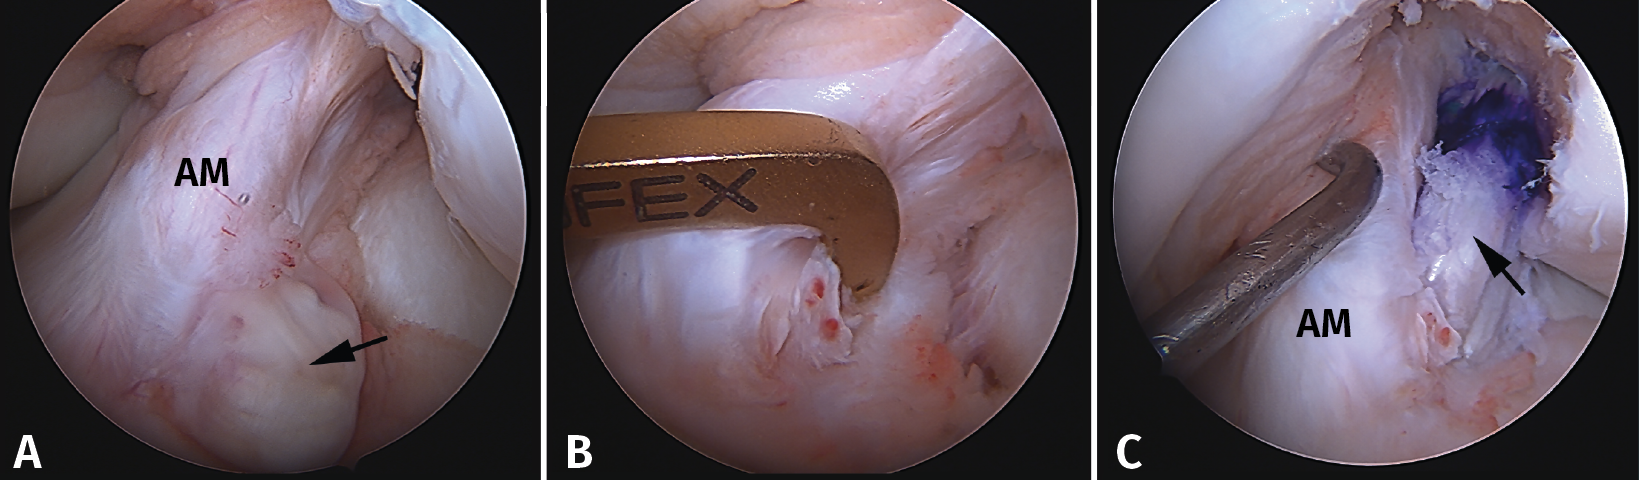

Figura 10. Plastia de reconstrucción selectiva unifascicular (fascículo posterolateral –PL–). A: imagen artroscópica de la rodilla izquierda desde el portal anterolateral. Se evidencia una rotura completa crónica del fascículo PL con remanente tibial (flecha) e integridad del fascículo anteromedial (AM); B: imagen artroscópica de la rodilla izquierda desde el portal anterolateral. Colocación de la guía tibial tomando el remanente como referencia en una reconstrucción selectiva del fascículo PL; C: imagen artroscópica desde el portal AM que muestra la plastia de reconstrucción selectiva-aumentación del fascículo PL con autoinjerto de isquiotibiales (flecha).

Técnicamente, en la reconstrucción selectiva del fascículo AM o PM es fundamental reproducir la huella anatómica, tanto en el fémur como en la tibia. La mejor referencia para conseguir una posición correcta es localizar el remanente del fascículo roto(33).